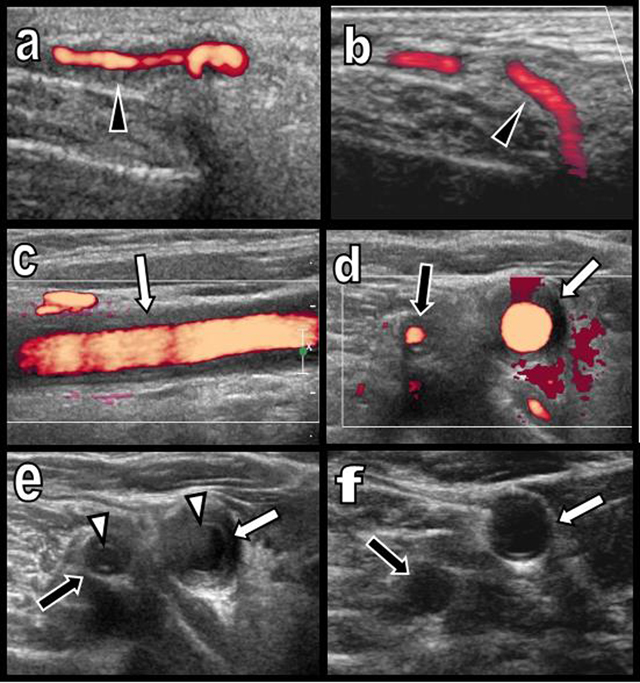

Figure 1

Colour Doppler Ultrasound of the temporal artery before (a) and after treatment (b) and of the right primitive carotid and vertebral arteries before (c, d, e) and after treatment (f).